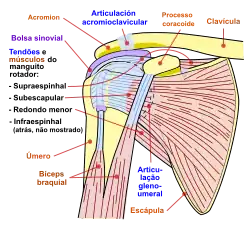

O úmero[1] é um osso longo e o maior do membro superior que se localiza no braço, articulando com a escápula, o rádio e com o cúbito, através das articulações do ombro e do cotovelo, apresentando na sua anatomia duas epífises[2], a proximal e a distal, e uma diáfise[3] constituídas por dezasseis acidentes anatómicos.[4]

Músculos que envolvem o úmero

- Bíceps Braquial

- Braquial Anterior

- Coracobraquial

- Tríceps Braquial